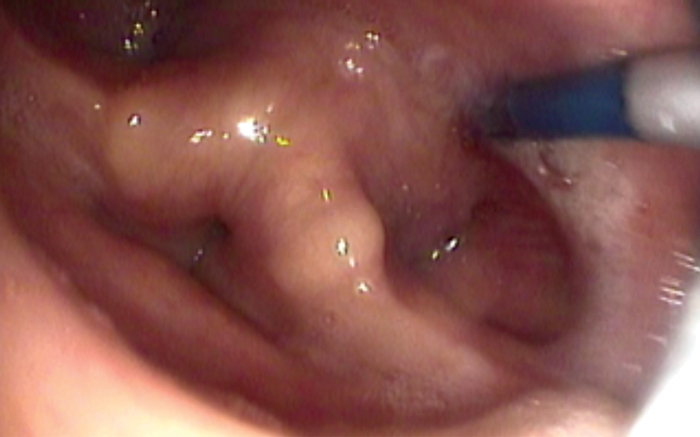

Once the tip of the guide wire is placed beyond the stricture, the TNO is reintroduced nasally via the most patent nasal cavity to visualise the pharynx during the dilatation. The uninflated balloon is then passed over the guide wire nasally until it passes through the area to be dilated. Both TNO and the balloon cables may be passed via same nostril if the other nostril is too narrow. The balloon is positioned with the proximal metallic silver marker visible just above the level to be dilated (see Figure 5). The balloon is then inflated using the pressure pump syringe until 20mm full dilatation (see Figure 6). This is then deflated after one minute and the balloon is removed with the guide wire. In some cases of webbing or cricopharyngeal bar, two 20mm balloons (40mm maximum) may be used simultaneously (see Figure 7). However, this carries a higher risk of perforation and it is more painful and, therefore, will need sedation in addition to the local anaesthesia.

Figure 5. Balloon being positioned in the cricopharynx.